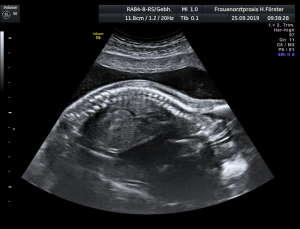

Gynäkologische Grundversorgung Frauenärztliche Krebsfrüherkennungsuntersuchung Nachsorge und supportive Therapie bei bösartigen gynäkologischen Tumoren Impfungen Brustultraschall Ultraschalluntersuchung der weiblichen Genitalorgane Psychosomatische Grundversorgung Chlamydienscreening FOB-Test (früher Hämoccult) Kontrazeption Geburtshilfliche Grundversorgung Geburtshilflicher Basisultraschall Erweiterter Basisultraschall (Organscreening) zw, 18-22.SSW Doppler/Duplexsonografie des fetomaternalen Gefäßsystems Infektionsscreening in der Schwangerschaft CTG (Kardiotokographie) Gynäkologische Grundversorgung Dies umfasst die Abklärung und Behandlung gynäkologischer Erkrankungen. Eine große Rolle dabei spielt das ärztliche Gespräch, ergänzt bei Notwendigkeit durch die gynäkologische Untersuchung oder Untersuchung der weiblichen Brust. In vielen Fällen werden noch Zusatzuntersuchungen durchgeführt (z.B. Ultraschalluntersuchungen, Abstrichentnahmen, Blutentnahmen) oder weiterführende Untersuchungen veranlasst (z.B. Röntgenuntersuchungen). >> zurück << Frauenärztliche Krebsfrüherkennungsuntersuchung Die Krebsfrüherkennungsuntersuchung der Frau ist wahrscheinlich die bekannteste Leistung unseres Fachgebietes. Ab dem Alter von 20Jahren hat jede Frau ein Anrecht auf diese jährliche Untersuchung. Dabei werden der Unterleib der Frau und ab dem Alter von 30Jahren auch die Brüste der Frau systematisch klinisch untersucht. Zusätzlich erfolgte seit vielen Jahren ein Pap-Abstrich vom Gebärmutterhals. So konnten Zellveränderungen meist rechtzeitig erkannt und behandelt werden und es wurde erreicht, daß das früher sehr häufige Zervixkarzinom (Gebärmutterhalskrebs) heute nur noch selten auftritt. Um die Qualität weiter zu verbessern erfolgte 2020 eine Neuordnung des Screenings mit Überarbeitung der Abstrichintervalle und Hinzunahme von HPV-Abstrichen ab 35 als Kassenleistung. >> zurück << Nachsorge und supportive Therapie bei bösartigen gynäkologischen Tumoren Nach Abschluss und oft auch wärend der Primärbehandlung können Probleme auftreten. Es macht also Sinn, sich in regelmäßigen Abständen zu treffen, um das weitere Vorgehen zu planen, eventuell Zusatzuntersuchungen zu veranlassen oder zusätzlich wegen der Beschwerden zu behandeln. Die Nachsorgeuntersuchungen finden anfangs engmaschig statt, später werden die Intervalle länger. >> zurück << Impfungen In Zeiten der Globalisierung, zunehmender Reisefreudigkeit und Zuwanderung werden wir wieder mit Infektionserregern konfrontiert, die wir schon als besiegt geglaubt hatten. Gleichzeitig werden wir immer älter und unser Immunsystem dabei nicht besser. Es reicht nicht, mal eben alle 10Jahre Tetanus zu impfen. Sind Sie geschützt? Wissen Sie was empfohlen ist? Bringen Sie den Impfausweis (auch den alten!!) mit. Wir prüfen Ihren Impfstatus, geben Ihnen Empfehlungen. Die gängigsten Impfstoffe haben wir auch vorrätig und können Sie impfen. >> zurück << Brustultraschall Die Ultraschalluntersuchung der Brust (Mammasonografie) kommt zur Abklärung von krankhaften Veränderungen zur Anwendung oder als Zusatzuntersuchung in der Früherkennung von Brustkrebs bei sehr dichtem Gewebe oder familiärer Vorbelastung. Sie ersetzt nicht das organisierte Mammographiescreening und ist nicht Bestandteil der normalen Krebsfrüherkennung. Es handelt sich um eine schmerzfreie Untersuchung ohne Strahlenbelastung. Die Mammasonografie  ist auch als Wunschleistung (IGeL) möglich. >> zurück << Ultraschalluntersuchung der weiblichen Genitalorgane Die Ultraschalluntersuchung der weiblichen Genitalorgane kommt zur Abklärung von krankhaften Veränderungen des weiblichen Genitales zur Anwendung. Dabei werden mit einer hochfrequenten Vaginalsonde die Organstrukturen im kleinen Becken untersucht. Die Untersuchung ist bei schlanken und sehr jungen Frauen auch vom Bauch aus möglich, die Genauigkeit ist dabei technisch bedingt aber schlechter.  Sie ist nicht Bestandteil der normalen Krebsfrüherkennung. Auch diese Untersuchung ist als Wunschleistung (IGeL) möglich. >> zurück << Psychosomatische Grundversorgung Jede Erkrankung belastet die Seele. Eine seelische Belastung macht den Körper krank. Jeder weiß das. Die Zusammenhänge zwischen dem kranken Körper und der kranken Seele beschreibt die Psychosomatik. Ein "Gordischer Knoten", der nur schwer zu zerschlagen ist, oft ein langer Weg. Ziel ist es, diese Zusammenhänge zu erkennen und den Betroffenen zu helfen ihren Weg zu finden. Oft ist die Zusammenarbeit mit einer Psychologin/ Psychologen nötig. Wichtig ist die Hilfe bei den ersten Schritten. Laufen müssen Sie selbst. >> zurück << Chlamydienscreening Das Bakterium Chlamydia trachomatis kann beim Sex übertragen werden und zu Entzündungen und sogar zur Unfruchtbarkeit führen. Deshalb bezahlen die Krankenkassen bis zum vollendeten 25.Lebensjahr allen sexuell aktiven Frauen einen Suchtest auf Chlamydien. Sie müssen lediglich eine Urinprobe abgeben. Auch in jeder Schwangerschaft wird nach Chlamydien gefahndet. Da Frauen im Normalfall auch im Alter über 25Jahren sexuell aktiv sind und noch schwanger werden wollen bieten wir die Testung auch als Wunschleistung (IGeL) an. Der Test wird dann aus einem Abstrich aus dem Muttermund entnommen, dies kann bei der Krebsfrüherkennung mit gemacht werden. >> zurück << FOB-Test (früher Hämoccult) Im Alter von 50 bis 54Jahren bezahlen die Krankenkassen allen versicherten Frauen einen Stuhltest zur Früherkennung von Darmkrebs oder seiner Vorstufen. Mit 55Jahren können Sie sich entscheiden zwischen zwei Darmspiegelungen im Abstand von 10Jahren oder der Fortführung der Stuhlteste alle 2Jahre. Natürlich kann man Stuhlteste auch zwischen den Darmspiegelungen machen lassen oder auch bei Frauen jünger als 50. Wir bieten dies als Wunschleistung (IGeL) unseren Patienten an. >> zurück << Kontrazeption Ein selbstbestimmtes Leben als Frau ist bei uns in Deutschland eine Selbstverständigkeit. Das war nicht immer so.  Kinder-Küche-Kirche hieß es früher, damals, in der guten alten Zeit. Das ist zum Glück vorbei. Und begonnen hat alles mit der Pille. Frauen konnten endlich über ihren Körper selbst bestimmen, ohne Angst ihre Liebe leben.  Aber die Pille ist nicht alles. Viele Märchen sind im Umlauf, Fehlinformation. Aber auch fehlendes Wissen zu Risiken.  Wir beraten Sie gern. >> zurück << Geburtshilfliche Grundversorgung In der Schwangerenberatung werden die werdenden Muttis gemäß den geltenden Mutterschaftsrichtlinien vom Anfang der Schwangerschaft bis zur Abschlussuntersuchung (6-8 Wochen nach der Geburt) betreut. >> zurück << Geburtshilflicher Basisultraschall Nach Vorgabe der Mutterschaftsrichtlinie sind sind in der Schwangerschaft 3 Ultraschalluntersuchungen vorgesehen. Diese finden in der 8.-12. SWW, in der 18,- 22. SSW und in der 28.-32.SSW statt. Dabei werden der Zustand des Embryos/ Feten, des Fruchtwassers und der Plazenta beurteilt. >> zurück << Erweiterter Basisultraschall (Organscreening) zw. 18-22.SSW Bei der zweiten Ultraschalluntersuchung (zw.18.-22. SSW) erfolgt ein erweitertes Screening mit Beurteilung der Organstrukturen des Kindes. Diese Untersuchung ist Kassenleistung, kann aber bei Wunsch auch Abgewählt werden, dann wird nur der Basisultraschall durchgeführt. >> zurück << Doppler/Duplexsonografie des fetomaternalen Gefäßsystems Bei Aüffälligkeiten im Schwangerschaftsverlauf oder auch bei bestimmten Vorerkrankungen oder Erkrankungen in einer früheren Schwangerschaft kann es notwendig sein die Durchblutung des Mutterkuchens und der Gefäße des Kindes zu Untersuchen. Hier kommt das Dopplerverfahren als Erweiterung des normalen geburtshilflichen Ultraschalls zum Einsatz. Dies erlaubt eine schnelle Zustandsbeurteilung des Kindes pepaart mit einer zeitlich begrenzten Vorhersage über die weitere wahrscheinliche Entwicklung. Bei entsprechender Indikation ist diese Untersuchung als Kassenleistung abrechenbar. >> zurück << Infektionsscreening in der Schwangerschaft Die Suche nach Krankheitserregern im Krankheitsfall ist Kassenleistung. Routinemäßig prüfen wir Ihren Schutz vor Röteln und Windpocken , in jeder Schwangerschaft erfolgt ein Test auf Chlamydien. Zusätzlich empfehlen wir jeder Schwangeren einen Test auf eine Besiedelung mit Gruppe-B-Streptokokken vor der Geburt. Diese Streptokokken können zu schweren Atemwegsinfektionen des Neugeborenen führen. Eine vorbeugende Behandlung bei positivem Test kann dann unter der Geburt erfolgen. Bei Wunsch kann auch ein erweitertes Erregerscreening über unser Labor erfolgen (Wunschleistung). Eine wichtige Rolle spielt auch die Kontrolle auf einen Schutz gegen eine Toxoplasmoseinfektion. Bei fehlendem Schutz empfielt sich die regelmäßige Testung aus dem Blut auf eine frische Infektion. Auch dies ist eine Privatleistung, wird aber von den meisten Kassen erstattet. Eine nicht erkannte und somit nicht behandelte Erstinfektion in der Schwangerschaft kann zu schweren Schäden beim Kind führen. >> zurück << CTG Ab etwa der 30.Schwangerschaftswoche können wir bei Notwendigkeit im Ramen der Schwangerschaftsvorsorge die kindlichen Herztöne (Kardiographie) und simultan dazu die die Spannung der mütterlichen Bauchdecke (Wehenschreiber, Tokographie) graphisch darstellen. Das nennt man zusammen Kardiotokographie oder kurz einfach CTG. Die Auswertung des CTG‘s erfolgt nach dem Fisher-Score (Punkte-System) sowie nach qualitativen Kriterien und erlaubt uns eine gute Zustandsbeurteilung des Kindes in den späteren Schwangerschaftswochen. >> zurück <<